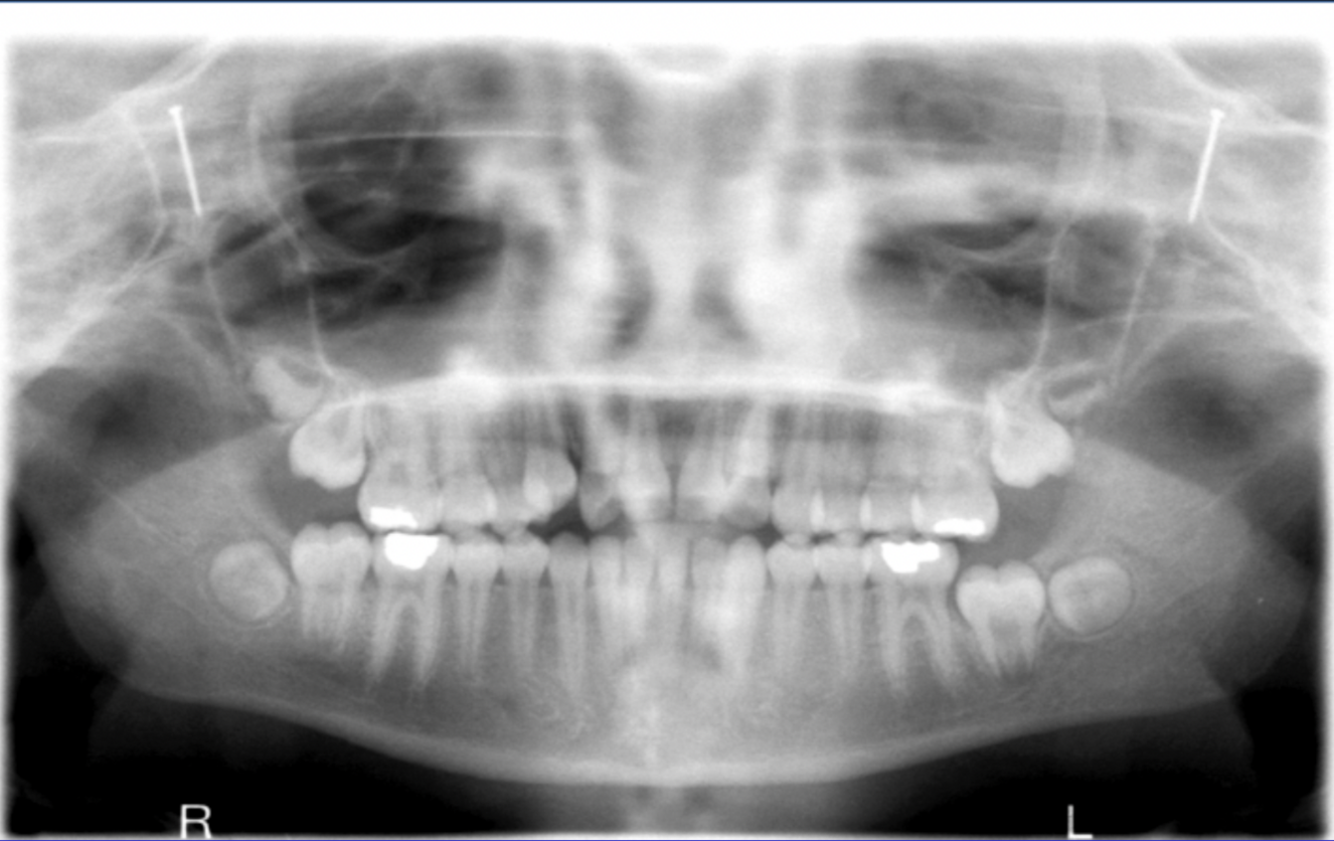

What error is seen in this pano?

What errors can be seen in the following radiograph? What is the cause?

1. excessive curvature of the occlusal plane 2. roots of mandibular anterior teeth are blurred 3. rami/condyles tipped inward 4. condyles close to or cut off top of image 5. hyoid bone superimposed on mandible cause: chin down